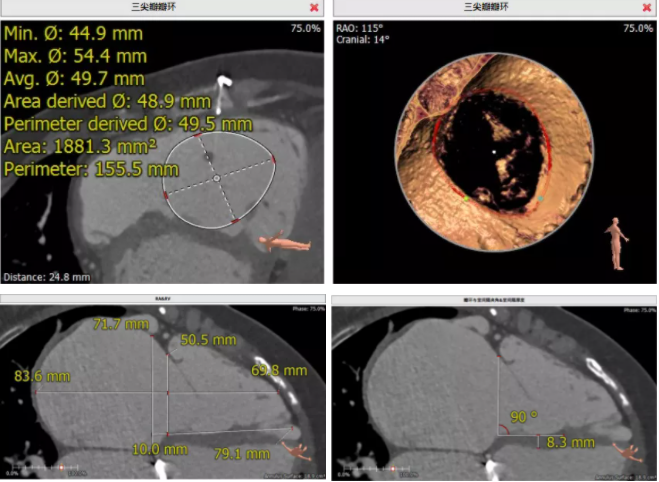

患者為68歲女性,14年前因“反復(fù)感冒、氣促”,檢查發(fā)現(xiàn)心臟瓣膜病,接受了“二尖瓣機(jī)械瓣置換術(shù)”。約5年前出現(xiàn)雙下肢水腫,活動后心累氣緊,心臟彩超提示:三尖瓣返流。近年來三尖瓣返流逐漸加重并伴有輕微黃疸、雙下肢水腫,雖長期服用利尿劑治療,但效果欠佳。郭惠明教授團(tuán)隊(duì)結(jié)合病史、超聲及CT評估,考慮患者瓣膜置換術(shù)后,三尖瓣重度返流,再次開胸行體外循環(huán)手術(shù)風(fēng)險高,經(jīng)團(tuán)隊(duì)整體評估,決定采用最適合患者的LuX-Valve三尖瓣置換系統(tǒng)行微創(chuàng)治療,根據(jù)測量結(jié)果選擇植入JS/TTVI-28-55型號的LuX-Valve瓣膜。